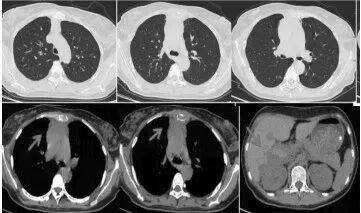

治疗前的医学影像图

第一个周期治疗后的医学影像图

令人欣慰的是,在医患双方的共同努力下,第一个周期治疗后,王女士的肿瘤明显缩小,血肌酐水平明显下降,肾功能逐步恢复。她成功脱离了血液透析,摆脱了对“人工肾”的依赖。目前,王女士病情稳定,已进入后续治疗阶段。